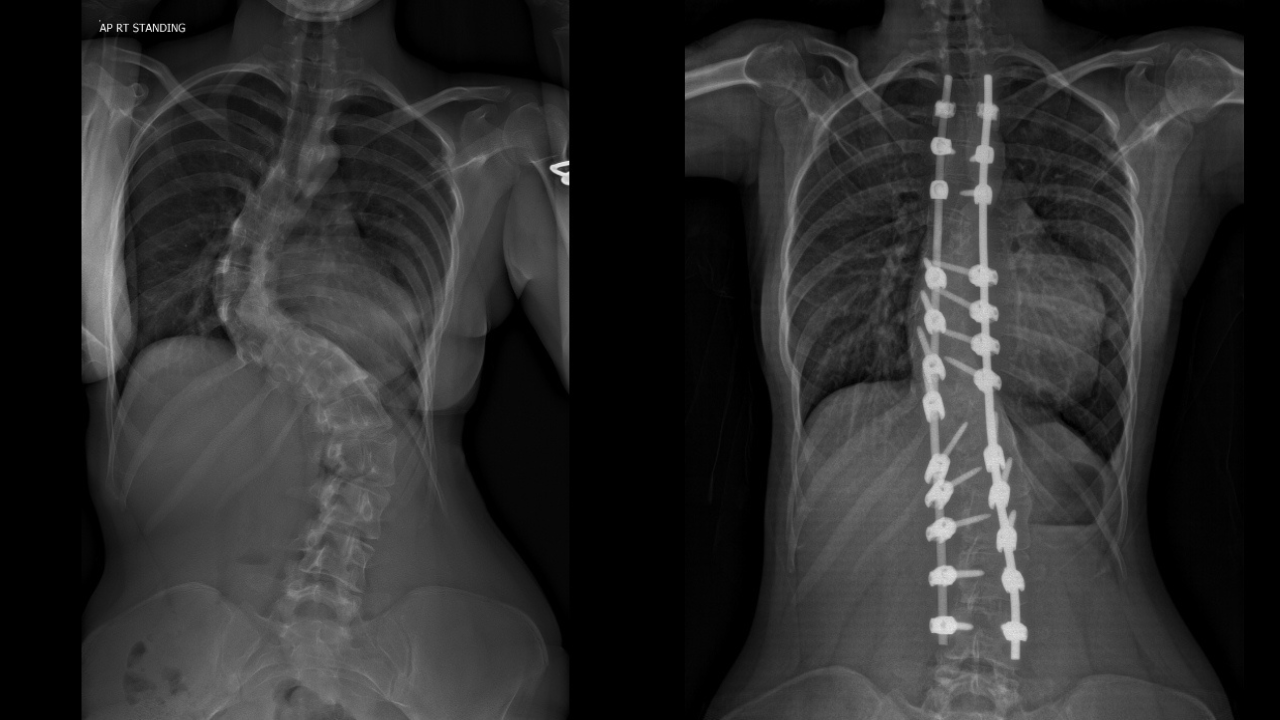

The 17-year-old underwent a complex nine-hour operation to correct curvature of her spinal column caused by scoliosis which she’d been diagnosed with as a baby.

In May last year Surgeons straightened and stabilised Daisy-Mai’s spine using rods and screws which fuse sections of it together and removed ribs to help correct the shape of her chest and improve her posture.

“Seeing the X-rays and realising how bad it was was terrifying.